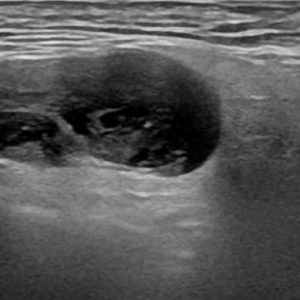

U tuyến nước bọt

Lượt xem: 138» 19-01-2021 -

U tuyến nước bọt

Lượt xem: 153» 19-01-2021 -

U tuyến nước bọt

Lượt xem: 131» 19-01-2021 -

U tuyến nước bọt

Lượt xem: 102» 19-01-2021 -

U tuyến nước bọt

Lượt xem: 146» 19-01-2021 -